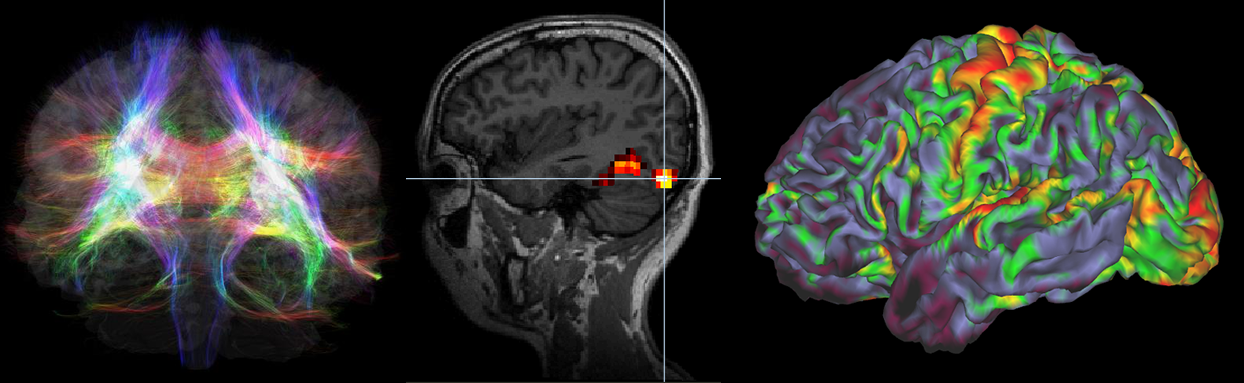

脑电波是大脑活动时发出的波状电信号。此前,受头骨覆盖等因素限制,人们能够捕捉到的脑电波信息有限。近年来,通过有效利用能读取大量数据的人工智能,在短时间内分析检测到的脑电波数据成为可能。脑电波研究专家、日本东北大学系统神经科学教授虫明元解释说,信息处理和分析技术的进步使得找到隐藏在脑电波中的各种信息成为可能。